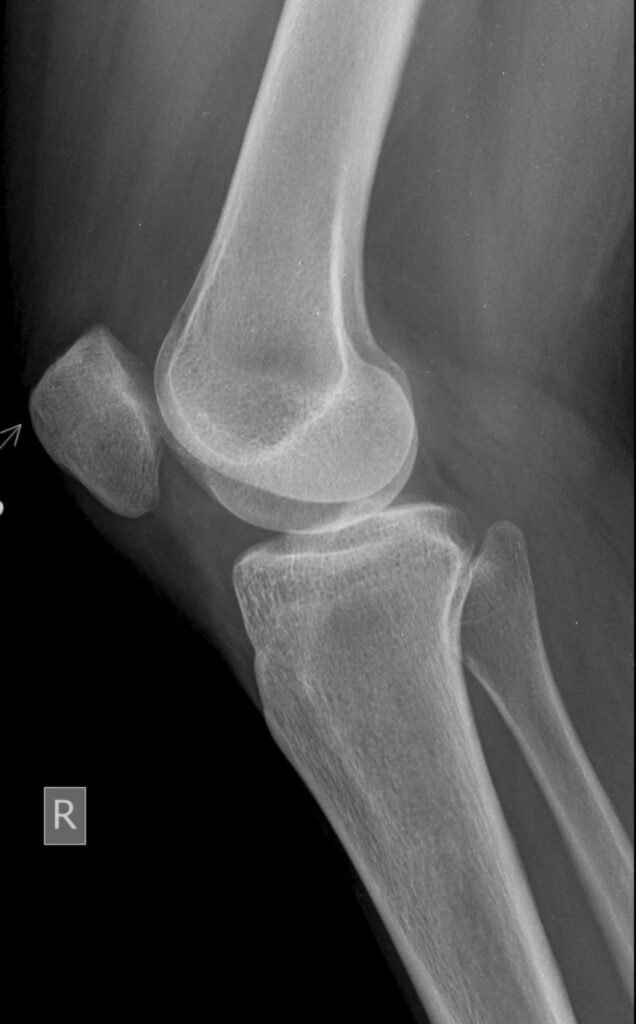

Existen varios tipos de articulaciones en el cuerpo humano, cada una con características específicas que determinan su función. Las articulaciones sinoviales, como las rodillas y los codos, son las más comunes y permiten una gran variedad de movimientos gracias a su diseño flexible. Otras articulaciones, como las cartilaginosas, que se encuentran en la columna vertebral, ofrecen estabilidad y soporte, aunque su capacidad de movimiento es más limitada.

Las articulaciones sinoviales son las más comunes en el cuerpo humano y se caracterizan por tener una cavidad llena de líquido sinovial. Este líquido actúa como un lubricante, facilitando el movimiento entre los huesos. Existen varios subtipos de articulaciones sinoviales, como las articulaciones de bisagra, que permiten el movimiento en una sola dirección, por ejemplo, en los codos y las rodillas; y las articulaciones esféricas, como la cadera y el hombro, que permiten una mayor libertad de movimiento en múltiples direcciones.